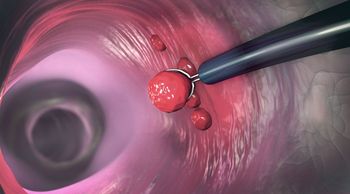

Vedolizumab proves to be superior to adalimumab for in achieving clinical remission and endoscopic improvement for ulcerative colitis, but not corticosteroid-free clinical remission.

Ustekinumab (Stelara, Janssen Biotech) was more effective at one year than placebo for inducing and maintaining remission in patients with moderate-to-severe ulcerative colitis, NEJM study shows.